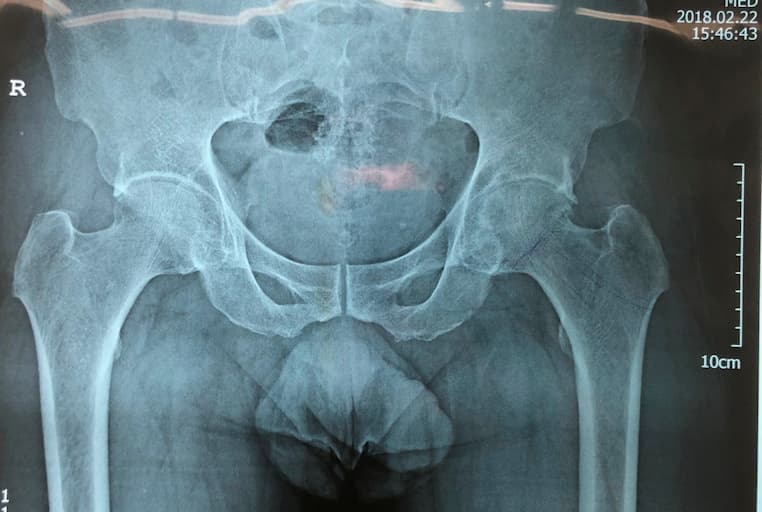

Түнхний толгой хэсгийн цусан хангамжийн алдагдалын улмаас үхжилт өөрчлөлттэй өвчтөний мэс заслын өмнөх болон дараах рентген зураг

Түнхний үе бүтэн солих мэс засал (THA) image1Түнхний үе бүтэн солих мэс засал (THA) image2